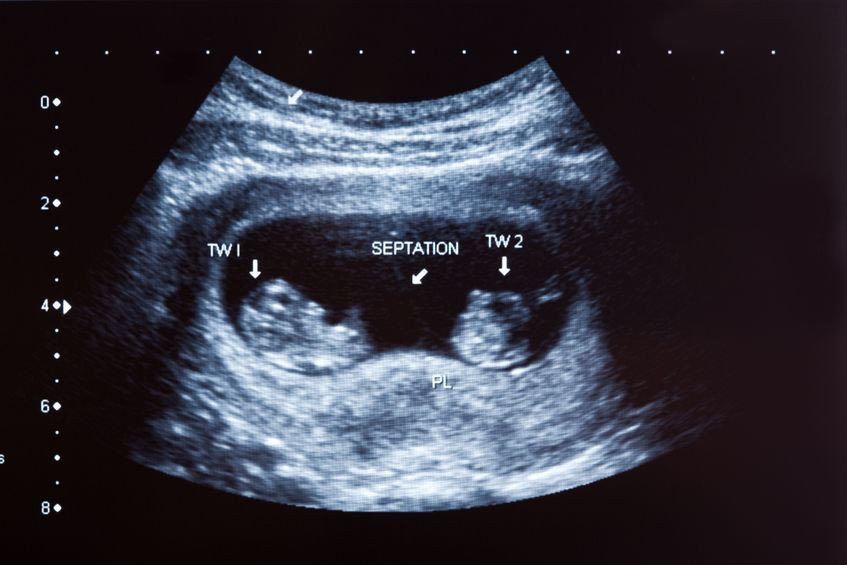

Norweskie Ministerstwo Zdrowia wydało oficjalne oświadczenie, z którego treści wynika, że kobiety będące w mnogiej ciąży, będą mogły dokonać aborcji… na jednym, wybranym płodzie. Zapis nie dotyczy bynajmniej płodów uszkodzonych, z poważnymi wadami genetycznymi. Wykonanie zabiegu jest możliwe bez specyficznych wskazań. Na jakiej podstawie można dokonać wyboru „płodu do redukcji”? I co to w ogóle za pomysł?

Lekarze są oburzeni, nie zgadzają się z decyzją polityków i mówią wprost: „Terminacja jednego z płodów jest nie tylko niewskazana, ale może stanowić bezpośrednie zagrożenie dla drugiego z nich i dla samej ciąży". Kto więc zaprojektował takie prawo, kto je przeforsował na arenie politycznej, na jakiej podstawie? Te pytania pozostają na razie bez odpowiedzi.

W Norwegii z roku na rok wzrasta liczba ciąż mnogich. Pojawiają się spekulacje, że to jeden z efektów powszechności stosowania metody in vitro. To prawdziwy absurd. Korzystanie z alternatywnej metody zapłodnienia, jaką in vitro bez wątpienia jest, zakłada w moim przekonaniu silną determinację do zostania rodzicem. Jak nazwać więc potrzebę usunięcia jednego z bliźniaczych płodów, kiedy ciąża staje się faktem? Kaprysem? Głupotą?